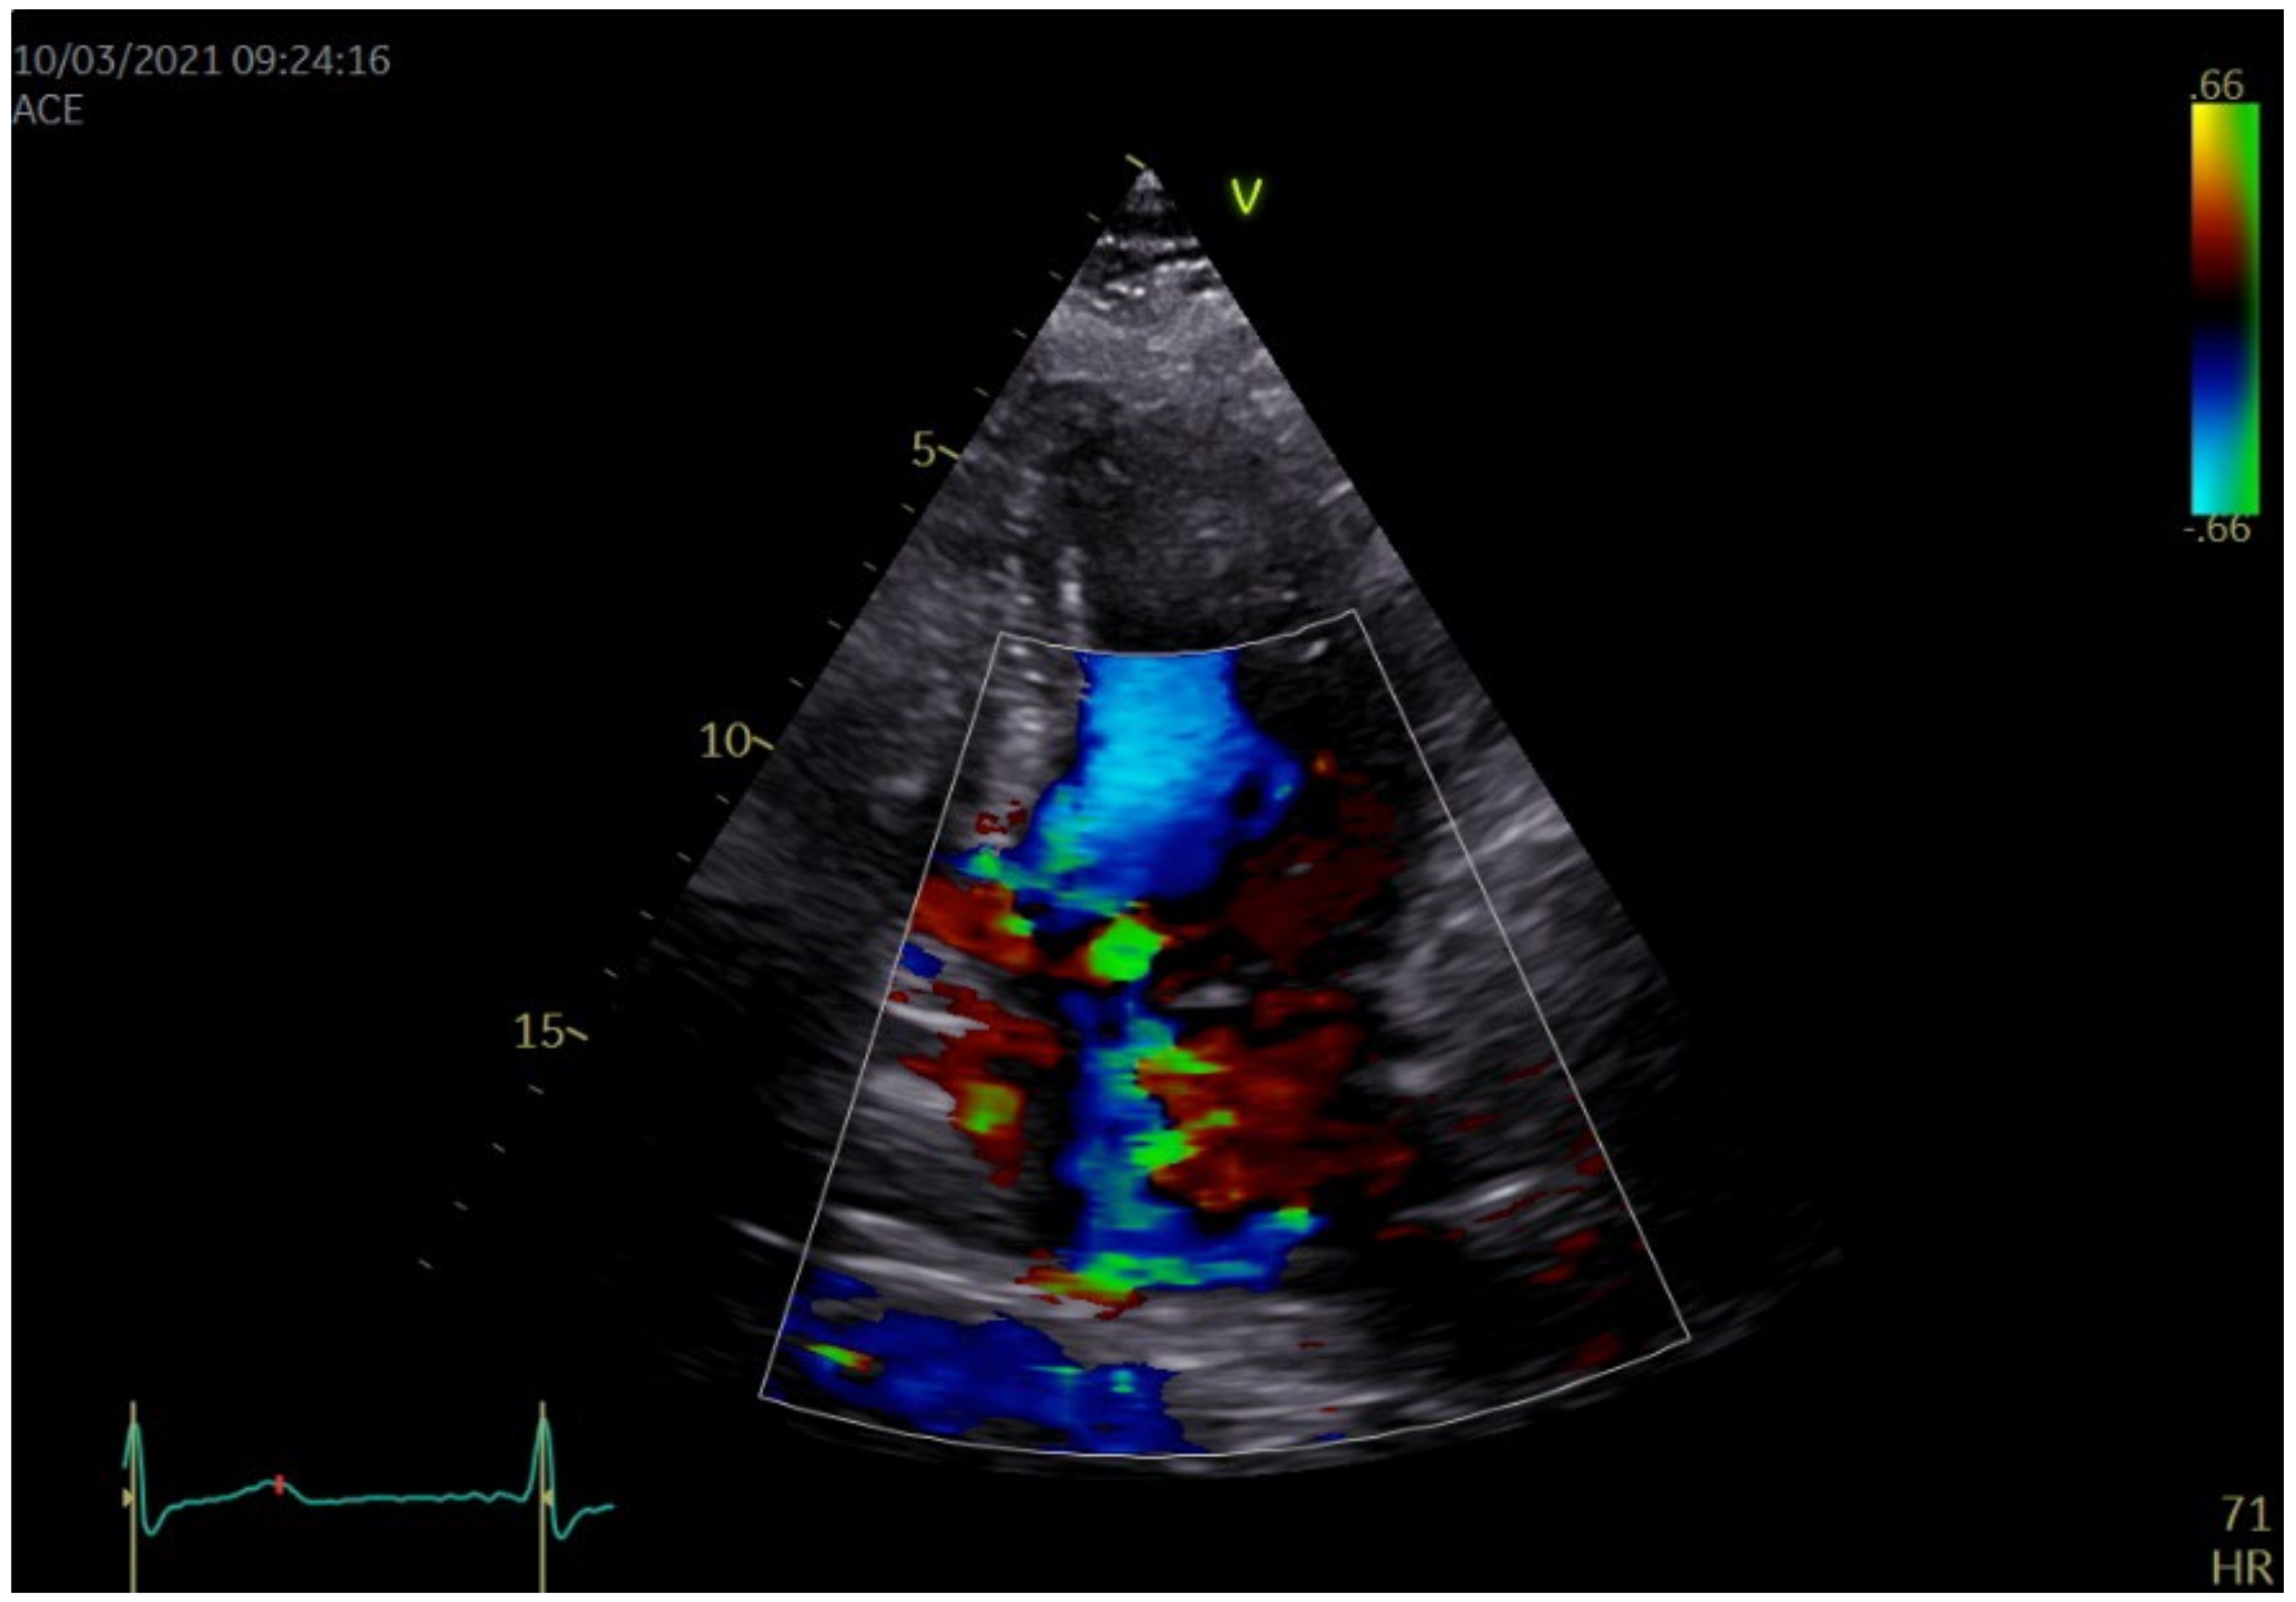

| Parameter | Value/Structure and Function Alteration |

|---|---|

| Chambers quantification | |

| Interventricular septum (IVS), mm | 21 |

| Left ventricular posterior wall (LVPW), mm | 15 |

| Left ventricular end-diastolic diameter, mm | 44 |

| Left ventricular end-diastolic volume, mL | 90 |

| Left ventricular ejection fraction (LVEF), % | 60 |

| S’ mitral annulus IVS/lateral wall, m/s | 0.08/0.10 |

| LV global longitudinal strain, % | −19.3 altered in the basal segments |

| LV twist, degrees | 8 |

| Left ventricular outflow tract maximal pressure gradient, mmHg | 100 |

| Left atrium (LA) diameter, mm | 49 |

| Right ventricular free wall, mm | 7 |

| Right ventricular diameter, mm | 27 |

| Tricuspid annular plane systolic excursion (TAPSE), mm | 25 |

| S’ tricuspid annulus, m/s | 0.16 |

| Right ventricular fractional area change (RV FAC), % | 40 |

| Valves quantification | |

| Mitral valve | Severe regurgitation |

| Aortic valve | Degenerated |

| Tricuspid valve | Moderate regurgitation |

| Pulmonary systolic arterial pressure, mmHg | 40 |

| Pulmonary valve | Minor regurgitation |